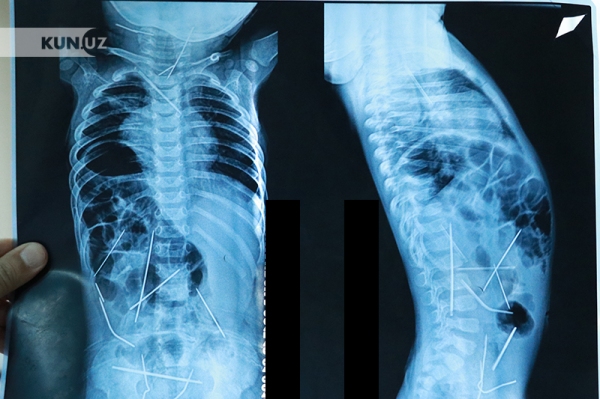

В Самаркандской области врачи извлекли из организма пациента около 200 г гвоздей и саморезов. Об этом сообщила пресс-служба областного филиала Республиканского научного центра экстренной медицинской помощи. nuz.uz »